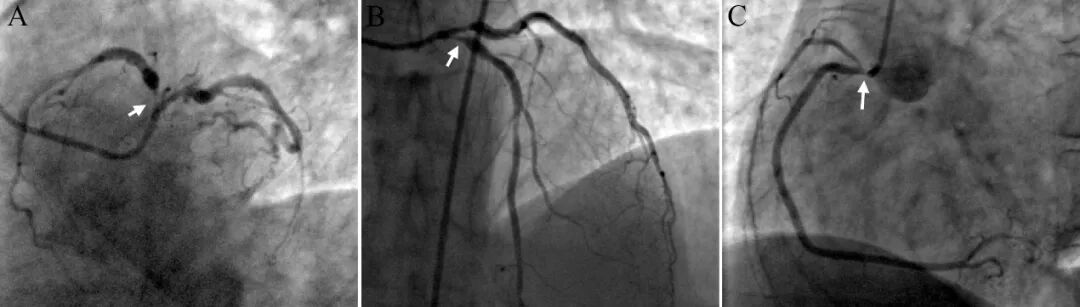

冠脉造影示严重三支开口病变:左主干狭窄80%,累及前降支开口狭窄99%,回旋支开口狭窄90%,右冠开口狭窄90%(图1)。

图1冠状动脉造影显示严重三支开口病变,箭头示狭窄部位